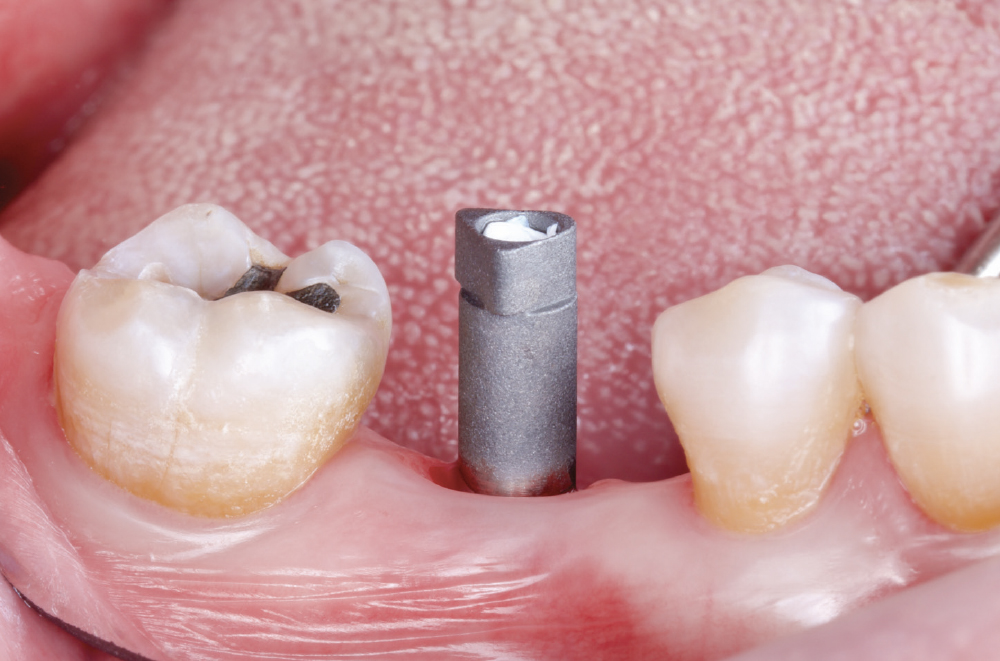

Verify Complete Scan Body Seating

Verify Complete Scan Body Seating. Confirm the scan body is fully seated to the implant before scanning — how it seats is precisely how the final restoration will seat. Use a radiograph if there is any question about complete seating, as an incompletely seated scan body will result in a restoration that does not fit, regardless of scan quality. Apply firm finger pressure or use a seating instrument, then verify there is no rocking or movement. Check for any tissue interference preventing complete seating and address it before scanning.

Capture the Surrounding Soft Tissue Immediately

Capture the Surrounding Soft Tissue Immediately. Scan the peri-implant soft-tissue architecture as soon as the scan body is placed, before the tissue collapse occurs. Gingival tissues begin to collapse and distort within minutes of scan body insertion, and the initial tissue contours are critical for creating proper emergence profiles. Work efficiently but thoroughly to document the tissue topography in its most accurate state.

Implant post scan on left side of mouth

Implant post scan pointing down

Implant post scan close up